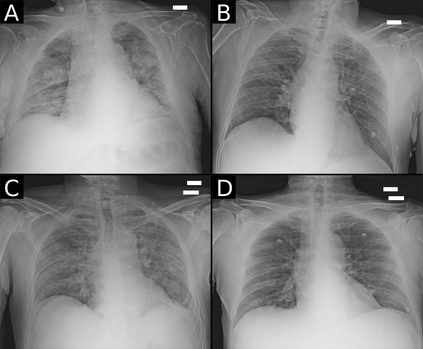

Recent epidemiological data report that worldwide more than 53 million people have been infected by SARS-CoV-2, resulting in 1.3 million deaths. The disease has been spreading very rapidly and few months after the identification of the first infected, shortage of hospital resources quickly became a problem. In this work we investigate whether chest X-ray (CXR) can be used as a possible tool for the early identification of patients at risk of severe outcome, like intensive care or death. CXR is a radiological technique that compared to computed tomography (CT) it is simpler, faster, more widespread and it induces lower radiation dose. We present a dataset including data collected from 820 patients by six Italian hospitals in spring 2020 during the first COVID-19 emergency. The dataset includes CXR images, several clinical attributes and clinical outcomes. We investigate the potential of artificial intelligence to predict the prognosis of such patients, distinguishing between severe and mild cases, thus offering a baseline reference for other researchers and practitioners. To this goal, we present three approaches that use features extracted from CXR images, either handcrafted or automatically by convolutional neuronal networks, which are then integrated with the clinical data. Exhaustive evaluation shows promising performance both in 10-fold and leave-one-centre-out cross-validation, implying that clinical data and images have the potential to provide useful information for the management of patients and hospital resources.